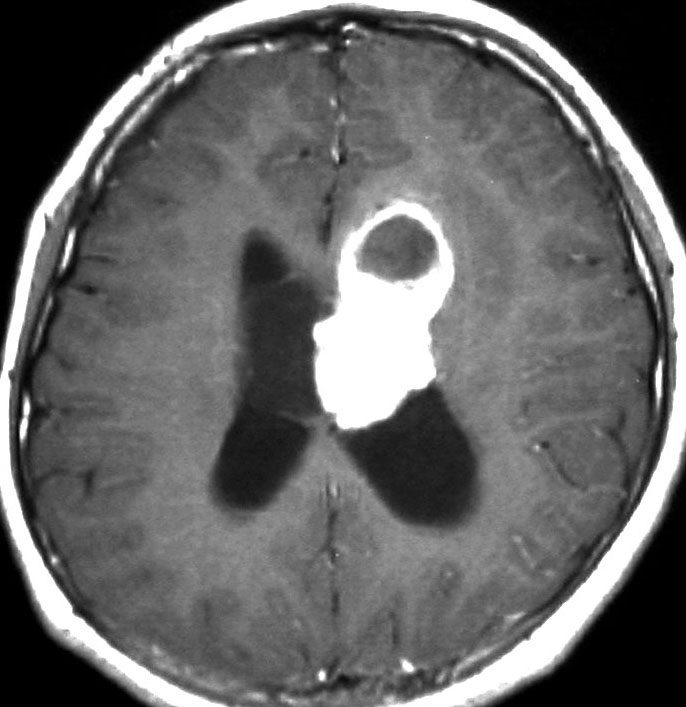

症候性の大きなSEGA

水頭症で発症した10歳の男の子のSEGAです。左側脳室の前角という部位から発生しました。腫瘍は右の脳室にものう胞を形成して,両側のモンロー孔を塞いだために閉塞性水頭症になって,頭痛と嘔吐が出ました。腫瘍の前方には腫瘍内出血もあります。

経皮質法 transcortical approachで摘出した後のMRI画像です。手術中には腫瘍からの出血は多く,深い位置にあり脳質壁を損傷しないように全摘出するのは難しいものでした。その後10年以上たっていますが再発していません。

この例は結節性硬化症を伴わないものでした。

central neurocytomaとの鑑別

孤発性SAGAの場合は側脳室内に発生する中枢性神経細胞種 central neurocytomaとの鑑別が難しいことがありますが,SEGAが尾状核頭に発生するのに対して,central neurocytomaが透明中核に発生することが多いので,腫瘍の位置で見分けることができます。central neurocytomaは両惻脳室中央,SEGAは惻脳室前方片側という特徴です。両者ともに閉塞性水頭症を呈して発症するので,巨大な腫瘍となっていることが多いし,両者ともに腫瘍内出血を生じることがあるので,これらは鑑別点となりません。

10歳の時に水頭症による頭痛と嘔吐で発症しました。結節性硬化症に合併したSEGAです。生検術,内視鏡手術,開頭術を受けて腫瘍を小さくして,その後にエベロリムスの投与を受けていました。これはエベロリムス投与後の画像です。この腫瘍にさらにエベロリムスの投与を続けるかという疑問があります。やめれば再燃することが多いからです。

結論として,これは完全摘出できるので摘出した方がいいです。なぜならそれでこの腫瘍は治癒するからです。右のFLAIR画像で見られるように発生部位となる尾状核のところでは一見,脳組織との境界が不明瞭にみえるのですが,腫瘍はある程度の硬さがあるので脳組織との区別をすることができて,完全摘出できるものです。